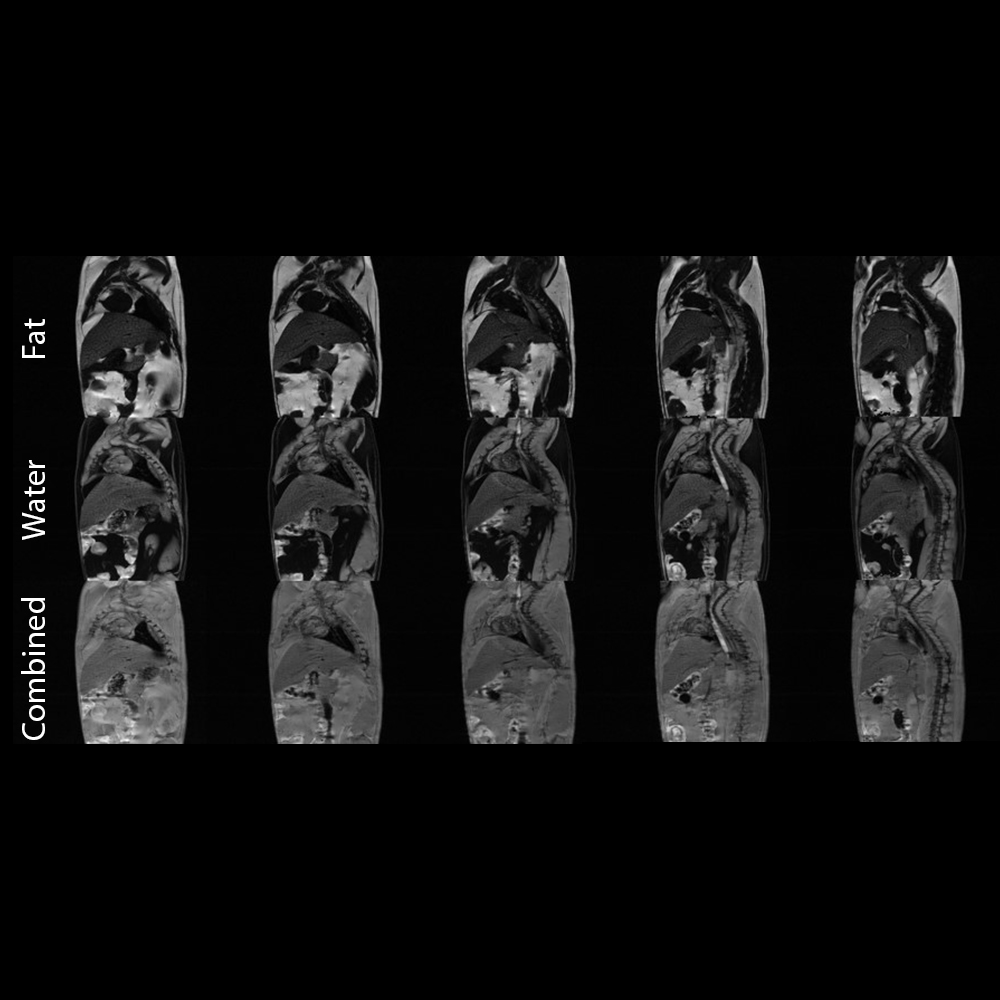

脂肪-水成像

基于多回波梯度回波序列的脂肪-水分离

〉动物模型:Wistar大鼠

〉序列:

多回波梯度回波

矩阵大小:256x256

视场:70毫米 x 50毫米,

厚度:1毫米 NEX:2,

采集时间:10分钟

〉线圈:72毫米Tx/Rx体积线圈